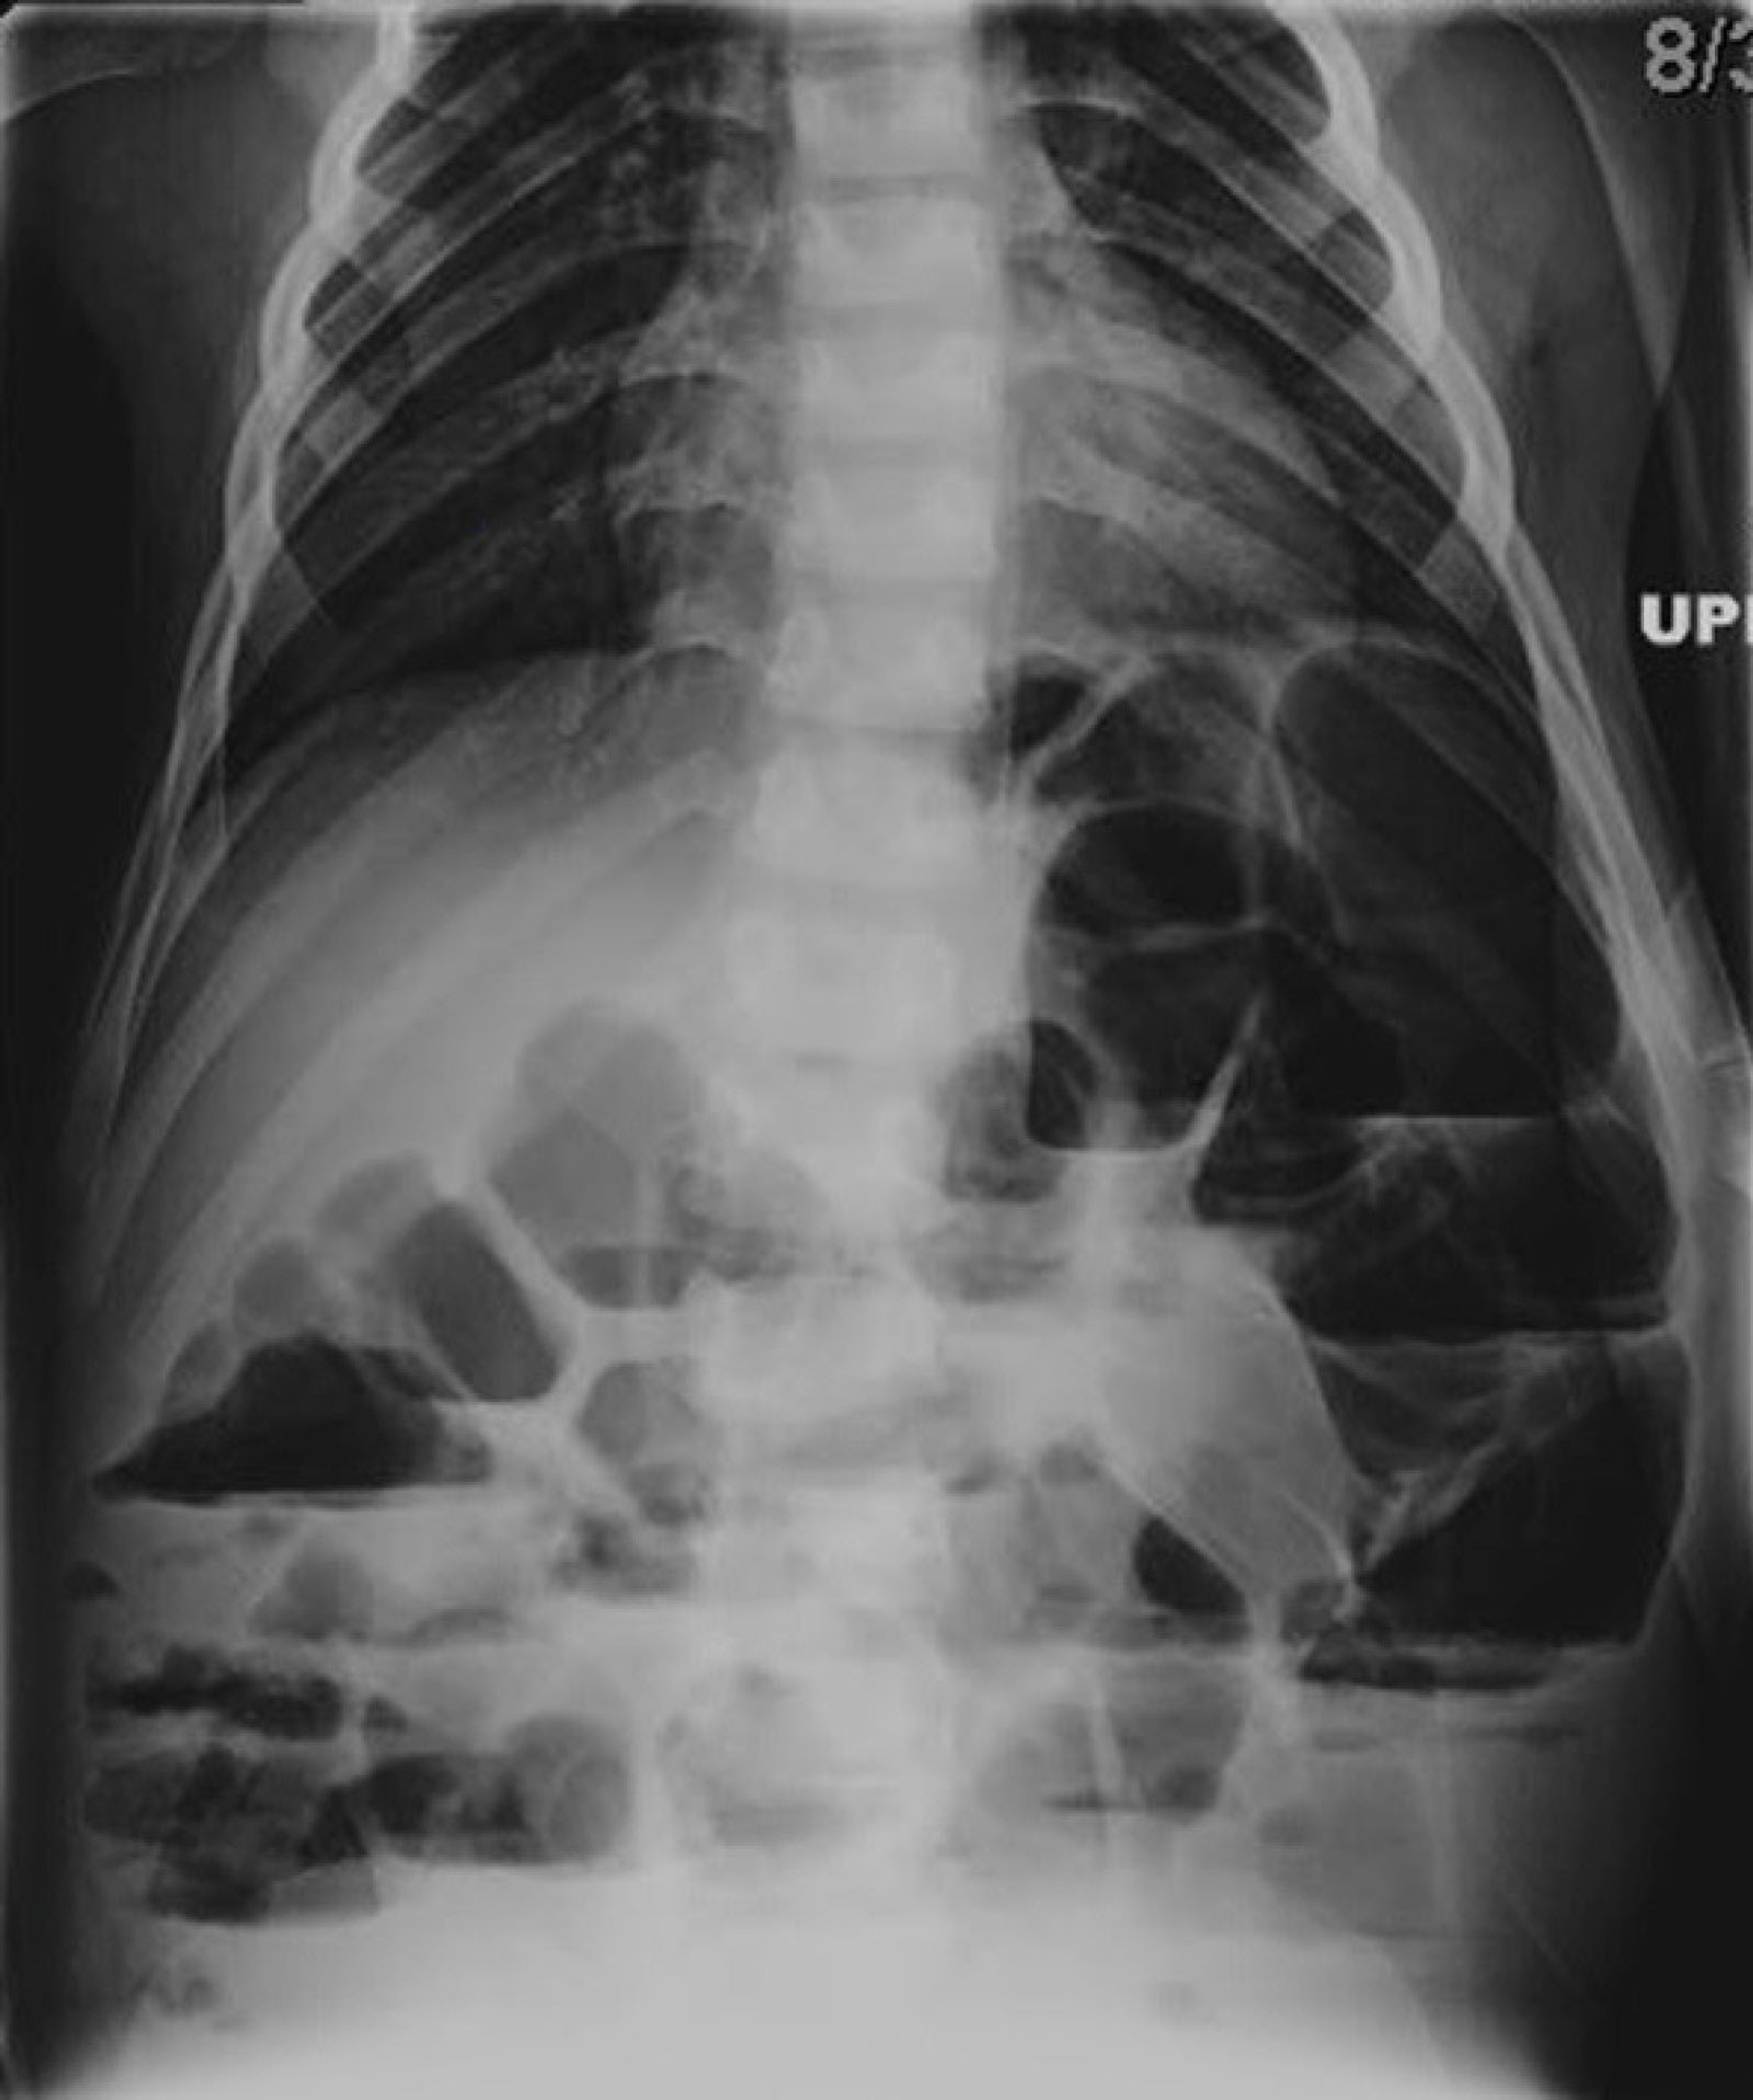

Ogilvie Bowel. In some cases the small bowel.

In some cases the small bowel.

Ogilvie Bowel In some cases the small bowel. In some cases the small bowel.